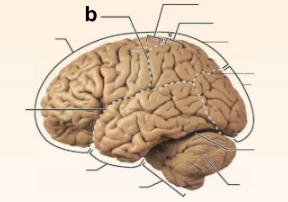

Identify the structure labeled “a” in the image.

Brain Stem

Identify the structure labeled “b” in the image.

Central culcus

Identify the structure labeled “c” in the image.

Cerebellum

Identify the structure labeled “d” in the image.

Frontal lobe

Identify the structure labeled “e” in the image.

Lateral sulcus

Identify the structure labeled “f” in the image.

Occipital lobe

Identify the structure labeled “g” in the image.

Parietal lobe

Identify the structure labeled “h” in the image.

Parieto-occipital sulcus

Identify the structure labeled “i” in the image.

Postcentral gyrus

Identify the structure labeled “j” in the image.

Precentral gyrus

Identify the structure labeled “k” in the image.

Temporal lobe

Identify the structure labeled “l” in the image.

Transverse cerebral fissure